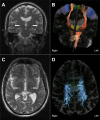

Neuroimaging in amyotrophic lateral sclerosis